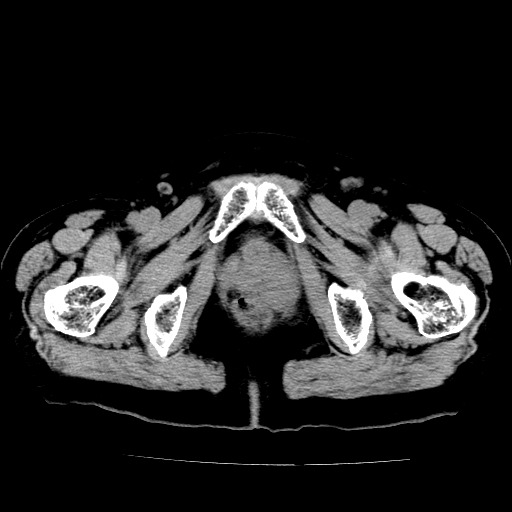

女,73岁,阴道流血一周。

宫颈不规则增大;结合临床考虑宫颈癌。建议作mri检查

1\\老年妇女突发阴道流血,常见病考虑宫颈癌.本病例宫颈部显示形态不规则,密度欠均匀,支持考虑宫 颈癌,建议mri 或阴道超声坚持

2\\但是盆腔两侧尚未见到明显肿大淋巴结等转移征象

宫颈不规则增大,左后方可见结节状突起.支持宫颈癌.

宫颈壁明显增厚,左侧为甚,宫颈癌待排,建议宫颈涂片细胞学检查。

宫颈不规则增大,周围脂肪间隙毛糙,结合临床考虑宫颈癌,盆腔内未见肿大淋巴结。